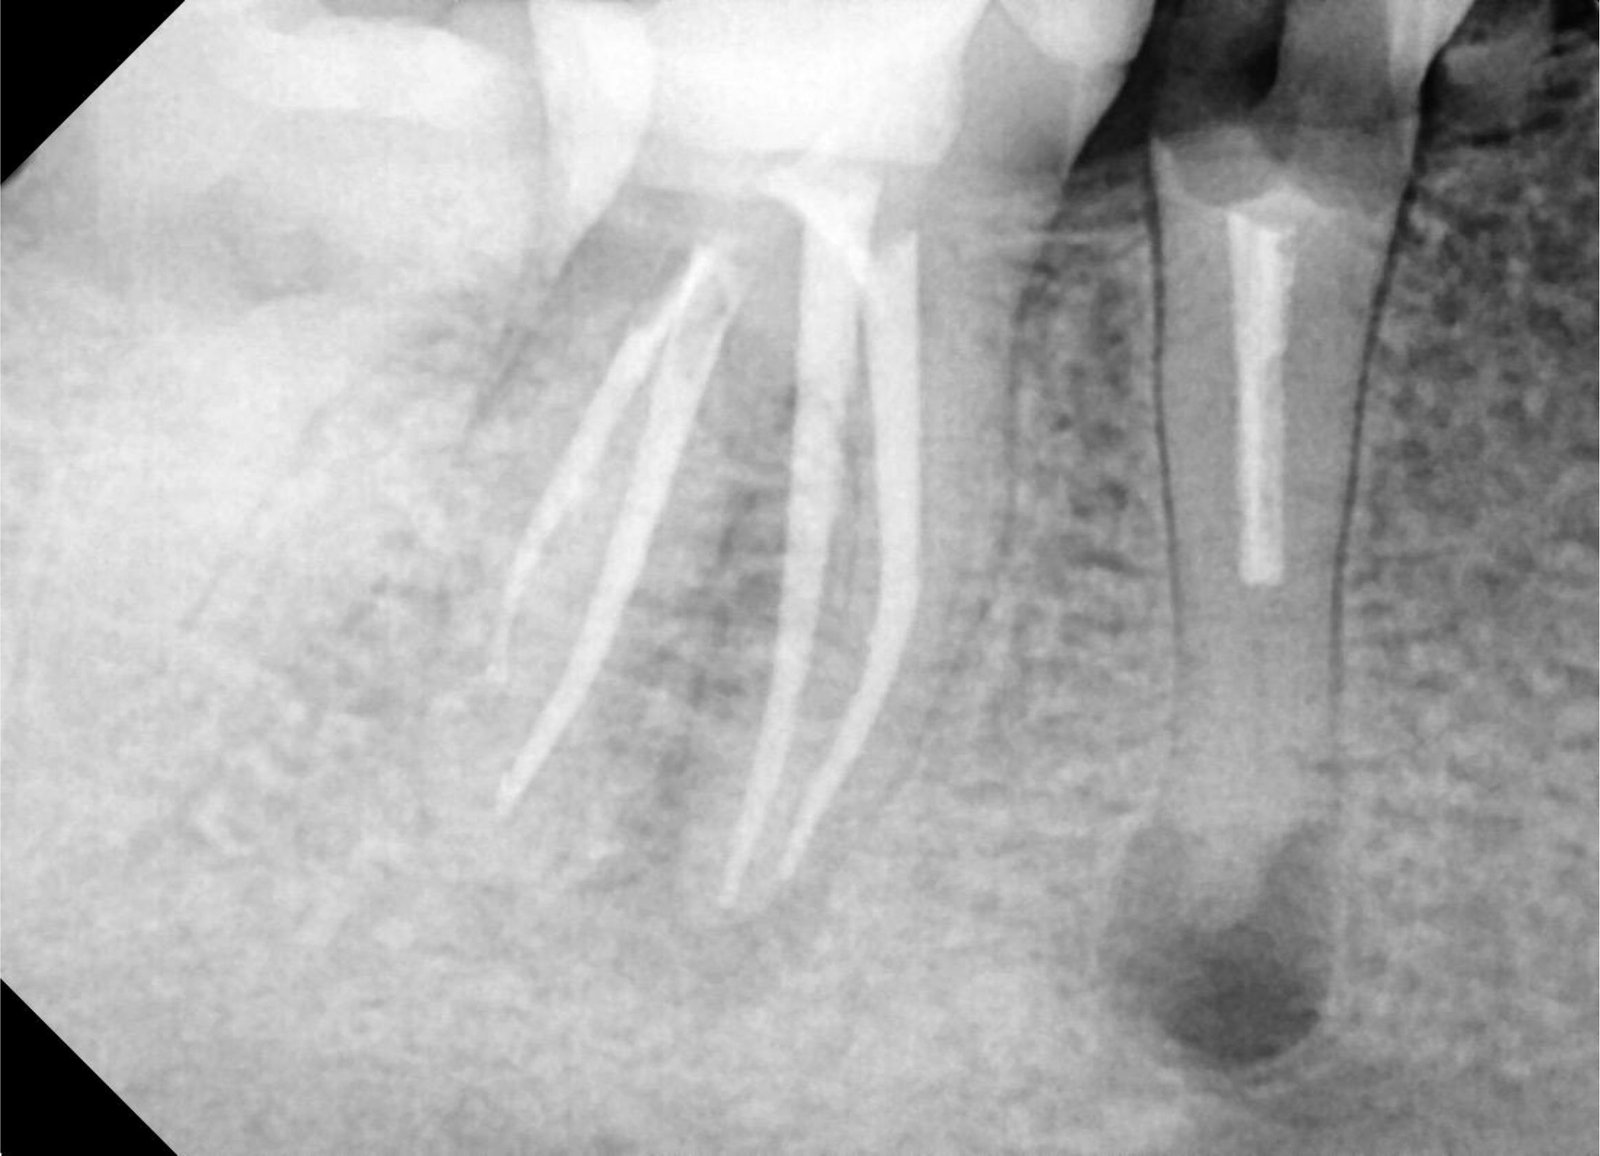

Rontgen Periapical digunakan untuk menunjukkan satu atau dua saja dengan lebih detail, biasanya rontgen Periapical digunakan untuk melihat kedalaman lubang dan apakah terdapat peradangan diujung akar.